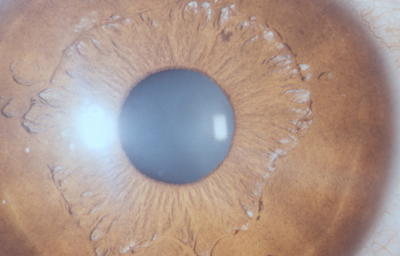

Alrededor del 7º mes la vascularización de la porción mesodérmica del Iris, (estroma iridiano) está llegando a su condición definitiva y el circulo vascular menor se reconoce; la túnica vasculosa lentis ya se ha atrofiado en sus porciones posterior y lateral, e inicia atrofia de su porción anterior (membrana pupilar) afectando en primer lugar su zona central; primero en las arcadas finales del centro los vasos se encogen, pierden circulación y quedan formando pequeñas espirales; el ectodermo iridiano con el esfínter ya se ha profundizado, está a nivel de las segundas arcadas vasculares de la membrana pupilar; cuando progresivamente la segunda arcada se atrofia, la membrana queda separada del margen pupilar y toma la apariencia de 2 capas: una anterior (la membrana pupilar) y otra posterior, el margen de la verdadera pupila. Esa grieta o seudoespacio tiene una extensión muy variable; por lo general, solo se ve en el borde de la pupila, pero puede ocurrir que comprometa la capa superficial de vasos periféricamente. Puede ocurrir que el proceso de atrofia no se detenga en la infancia y continue lentamente a lo largo de la vida, hasta que al final toda la hoja vascular anterior se separe del estroma profundo y quede flotando libre en la cámara anterior unida únicamente en la máxima periferia al estroma iridiano (Iridosquisis).

Lo que generalmente se ve, son parches de atrofia localizados periféricamente al margen pupilar, que toman la apariencia de criptas en el estroma.

El modelado final del Iris adulto, tendrá gran cantidad de variaciones dependientes de la cantidad de atrofia de su hoja anterior y de la pigmentación que desarrolle.